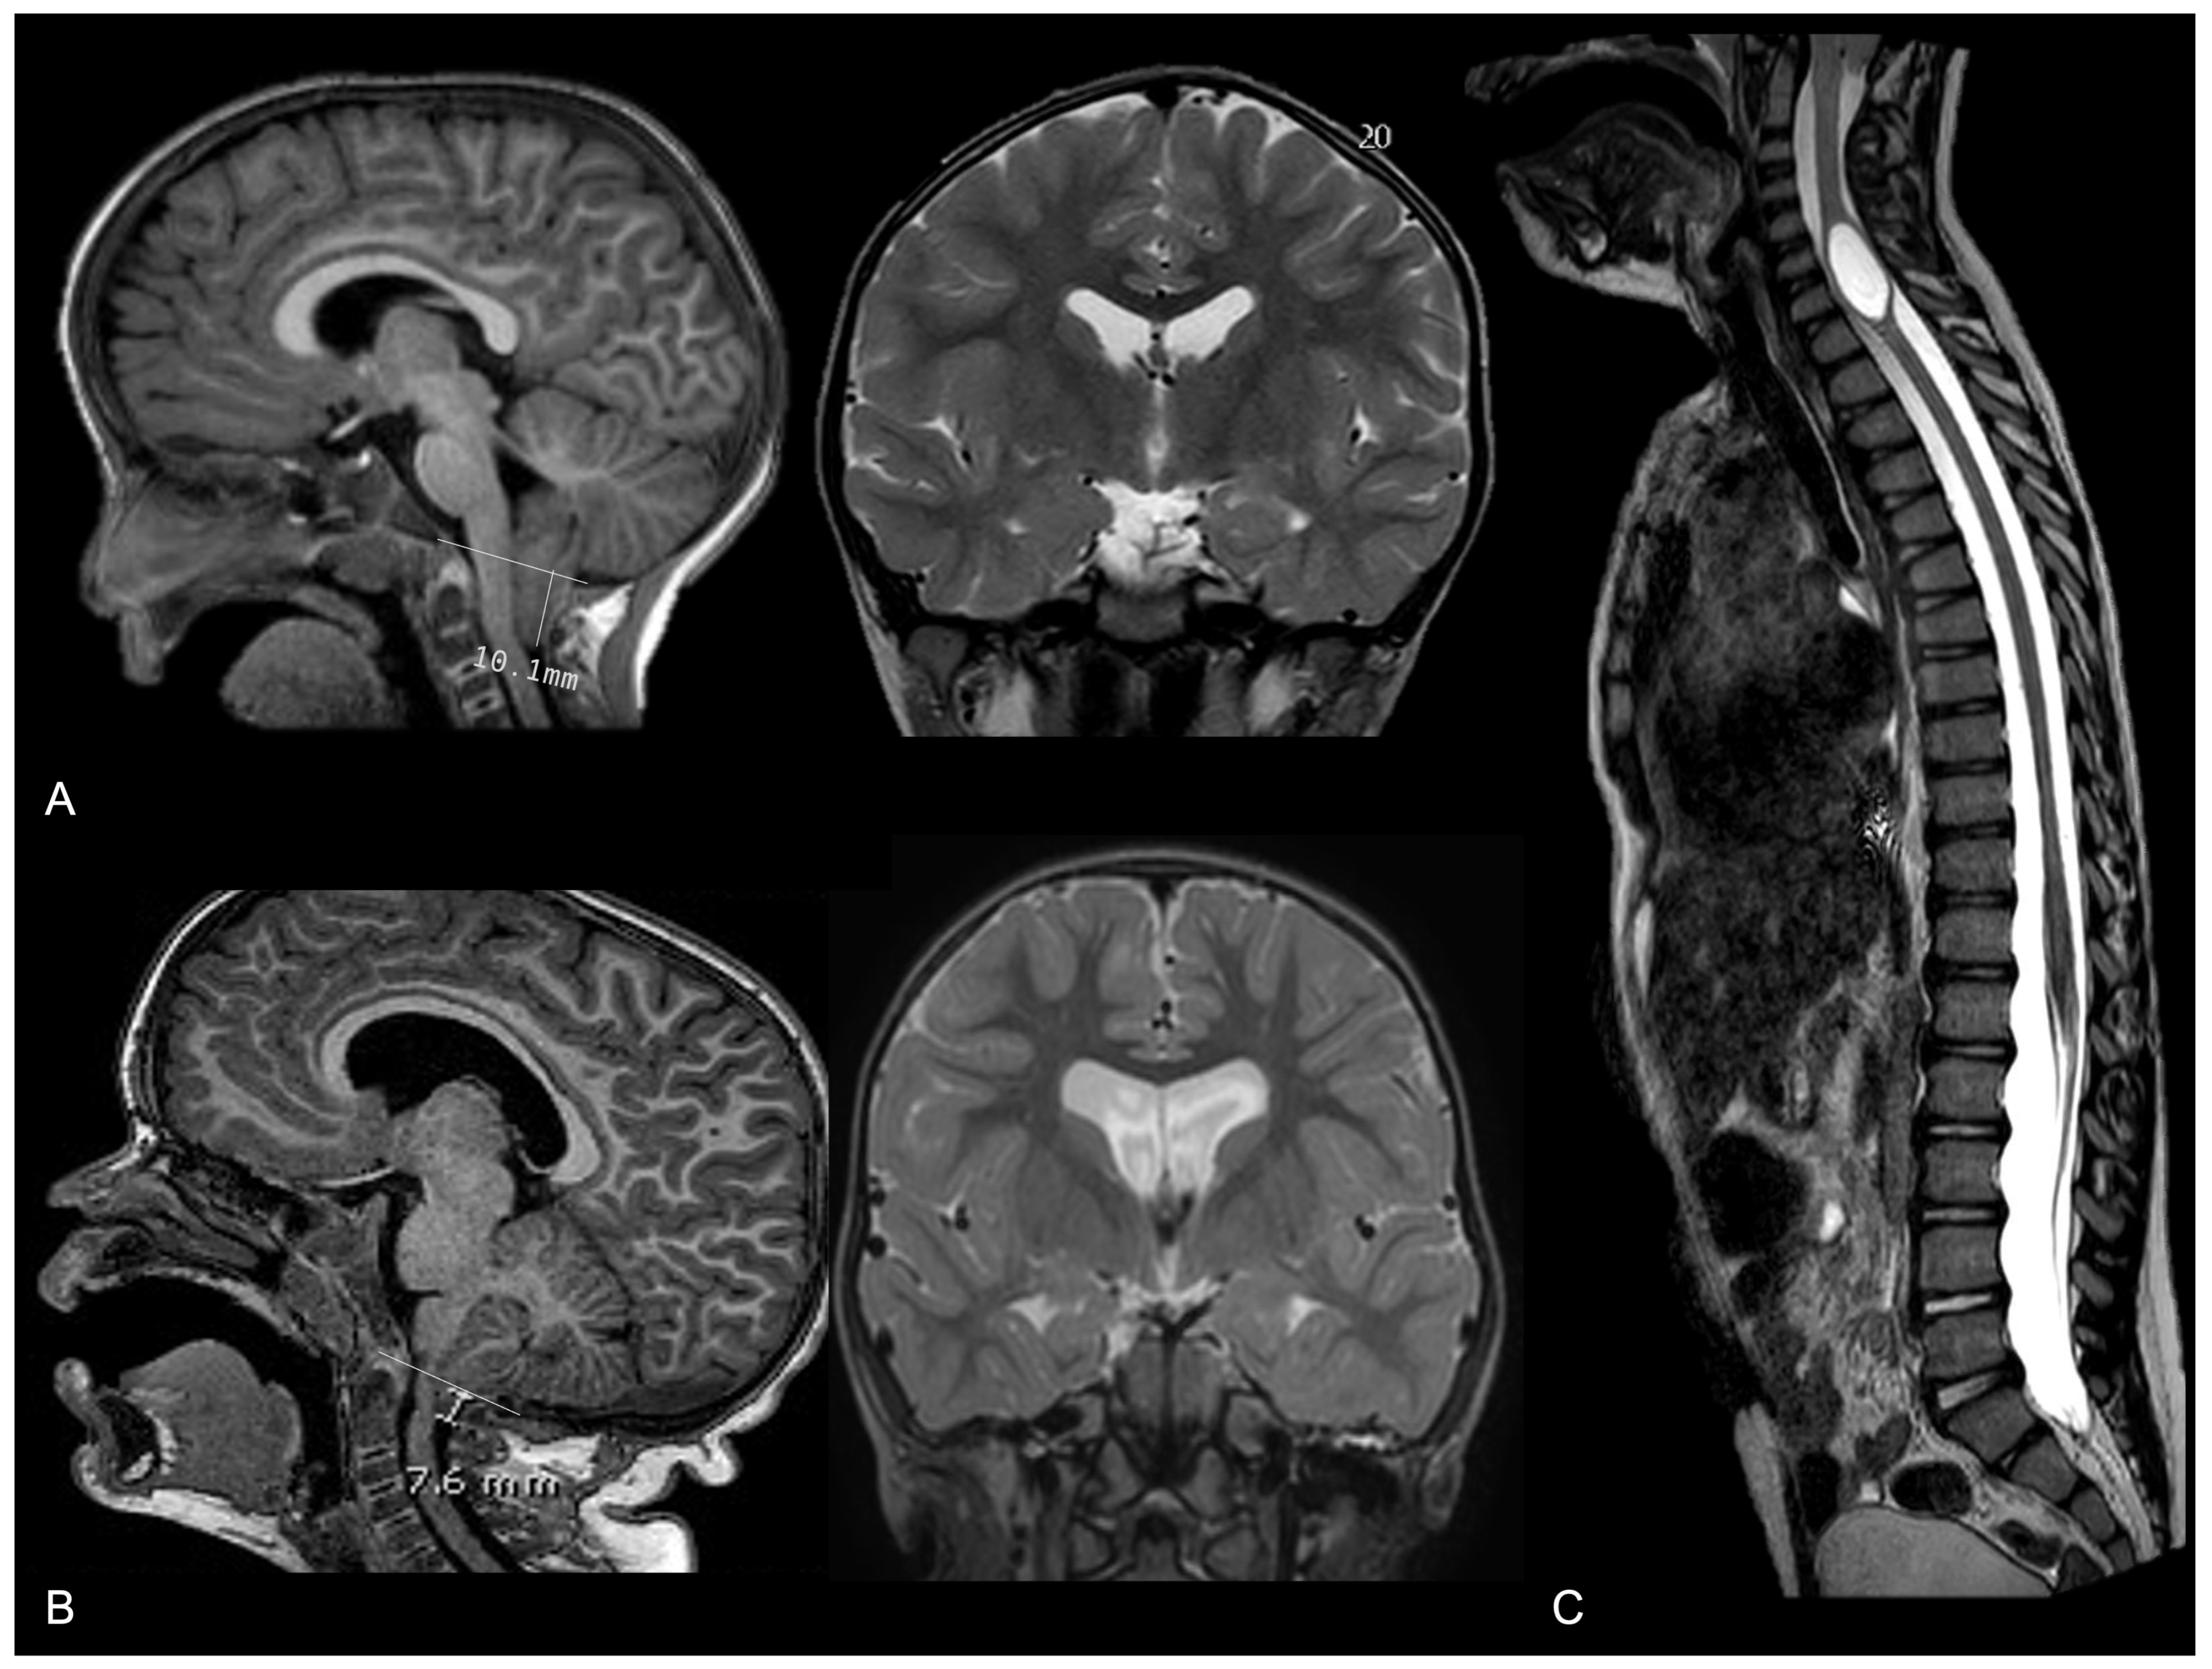

- Cinalli, G.; Spennato, P.; Sainte-Rose, C.; Arnaud, E.; Aliberti, F.; Brunelle, F.; Cianciulli, E.; Renier, D. Chiari malformation in craniosynostosis. Child’s Nerv. Syst. 2005, 21, 889–901. [Google Scholar] [CrossRef] [PubMed]

- Strahle, J.; Muraszko, K.M.; Buchman, S.R.; Kapurch, J.; Garton, H.J.L.; Maher, C.O. Chiari malformation associated with craniosynostosis. Neurosurg. Focus 2011, 31, E2. [Google Scholar] [CrossRef]

- Saletti, V.; Farinotti, M.; Peretta, P.; Massimi, L.; Ciaramitaro, P.; Motta, S.; Solari, A.; Valentini, L.G. The management of Chiari malformation type 1 and syringomyelia in children: A review of the literature. Neurol. Sci. 2021, 42, 4965–4995. [Google Scholar] [CrossRef]